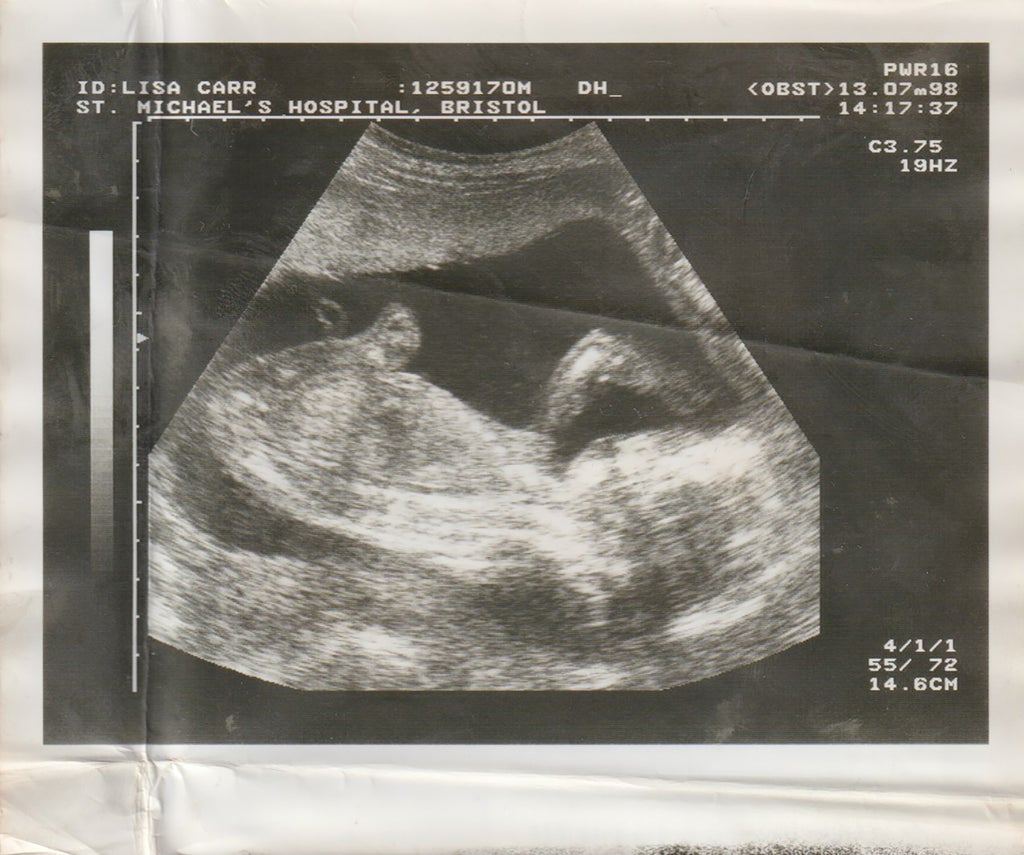

“I was two weeks into my master’s course when I found out I was pregnant,” says 24-year-old photographer Jade Carr-Daley. “At the time, I had already started a body of work focusing on my relationship with being both British and Jamaican but it was moving slowly and, in all honesty, I hadn’t been feeling that strongly towards it.” While searching for a topic that felt more fulfilling, Carr-Daley began taking photos to document her transition into motherhood – just for herself at first, until three months later when she finally decided to acknowledge what was staring her in the face: this documentation should be her major project. “It seemed so natural and free-flowing,” she says, “like this was the project I was meant to make.”

“The first three months of my pregnancy were the hardest,” she recalls. “At the time, only my partner and I knew and during this time, I experienced some issues with bleeding, spent a lot of time being assessed and was constantly worried something was wrong or that I had done something I shouldn’t have. As a result, I fell into a sort of hole, and found it hard to talk about my feelings. So when I started photographing myself and my environment, it turned into a form of self-therapy for me. Instead of being in that moment and state of mind alone, I was able to photograph it and this made it easier to understand how I was feeling, to see my physical changes and to better articulate how I felt about certain situations to my loved ones and friends.”